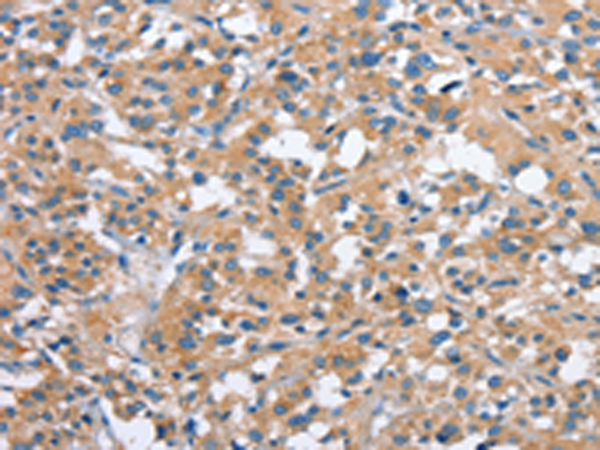

分类: 科研抗体货号: P07511别名: RK; p38; CSBP; EXIP; Mxi2; CSBP1; CSBP2; CSPB1; PRKM14; PRKM15; SAPK2A; p38ALPHA应用: IHC反应种属: Human, Mouse, Rat